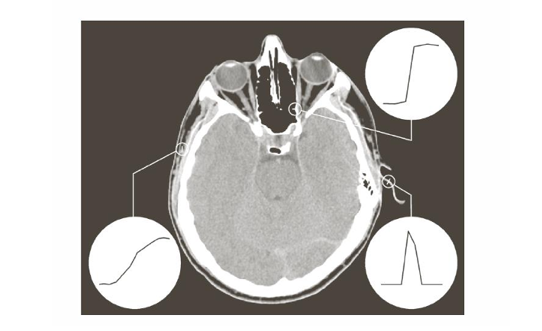

이상적인 엣지는 밝기 변화의 패턴에 따라 크게 세 가지로 모델링할 수 있다.

한쪽 영역에서 다른 영역으로 밝기가 갑자기 변하는 형태로, 픽셀 강도가 일정하다가 경계에서 순간적으로 변화가 발생한다.

예를 들면, 물체의 뚜렷한 경계, 명암 대비가 큰 부분 등이 있다.

밝기가 점진적으로 변하는 형태이다. 실제 영상에서 흔히 발생하며,(카메라 초첨, 센서 특성, 모션 블러 등의 영향으로 경계가 흐려짐) 경계 구간의 폭이 step edge보다 넓다.

밝기가 특정 위치에서 최대(최소)를 이루고 양쪽으로 완만하게 감소한다. 얇은 선이나 가느다란 구조에서 나타나는 패턴이다.

예를 들면, 머리카락, 혈관, 회로 기판의 선 등이 있다.

CT 영상 예시를 확인해보면, 위 세 가지 모델이 나타남을 확인할 수 있다. Step Edge는 뼈와 연조직 경계처럼 명확하게 구분되는 영역, Ramp Edge는 연부 조직과 같은 경계가 흐린 부분, Roof Edge는 혈관, 가느다란 구조물 등에서 보인다.

각 모델의 실제 프로파일(밝기 값 변화)를 보면, 이상적 모델과 매우 유사하게 나타나며, 엣지 검출 알고리즘은 이러한 밝기 변화 패턴을 이용해 경계를 찾는다.